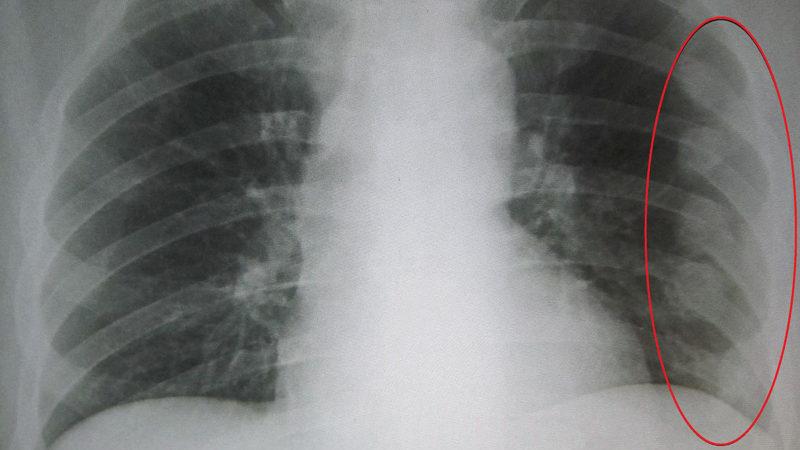

Гемоторакс возникает, когда кровь попадает в легкие. Это состояние можно диагностировать только с помощью рентгенографии.